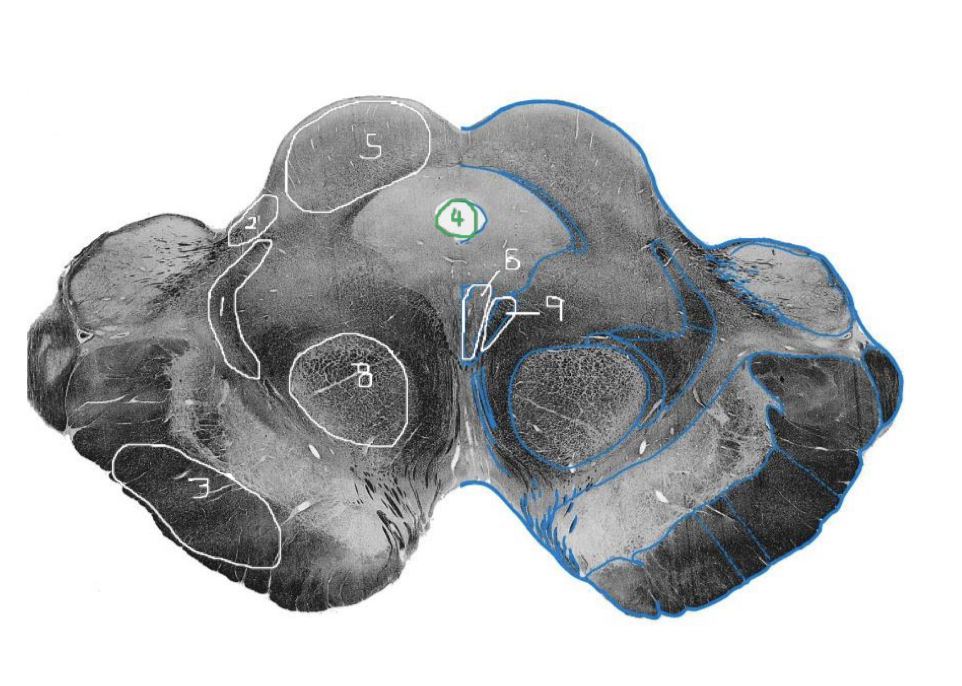

1

Medial Lemniscus - Rostral Pons

2

Spinothalamic Tract - Rostral Pons

3

CST - Rostral Pons

4

Cerebral Aqueduct - Rostral Pons

5

Middle Cerebellar Peduncle - Rostral Pons

6

Superior Cerebellar Peduncle - Rostral Pons

7

Medial Longitudinal Fasciculus (MLF) - Rostral Pons